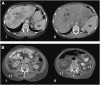

Design: A longitudinal computed tomography (CT) image review was performed to quantify organ size (liver, including metastases, and spleen) and peripheral tissues (skeletal muscle and adipose tissue) during colorectal cancer cachexia progression (n = 34). Body composition was prospectively evaluated by CT and dual-energy X-ray absorptiometry, and REE was determined by indirect calorimetry in advanced colorectal cancer patients (n = 18).

Results: Eleven months from death, the liver (2.3 +/- 0.7 kg) and spleen (0.32 +/- 0.2 kg) were larger than reference values. One month from death, liver weight increased to 3.0 +/- 1.5 kg (P = 0.010), spleen showed a trend to increase (P = 0.077), and concurrent losses of muscle (4.2 kg) and fat (3.5 kg) (P < 0.05) were observed. The estimated percentage of fat-free mass (FFM) occupied by the liver increased from 4.5% to 7.0% (P < 0.001). The most rapid loss of peripheral tissues and liver and metastases gain occurred within 3 mo of death. A positive linear relation existed between liver mass and measured whole-body REE (r(2) = 0.35, P = 0.010); because liver accounted for a larger percentage of FFM, measured REE . kg FFM(-1) . d(-1) increased (r(2) = 0.35, P = 0.010).